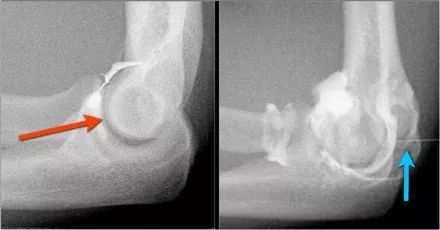

肘关节脱位这是一个患者肘部的侧位片。X光片显示关节积液(红色箭头)和冠状突骨折(黄色箭头)。

下面是MR● 冠状图片:侧副韧带完全剥离(黄色箭头)。桡骨头是半脱位的。由于骨折引起的冠突骨髓水肿(红色箭头)。● 矢状面观:桡骨头稍后有点半脱位(黄色箭头)。大量积液和囊后破裂。● 由于冠状突的撞击(红色箭头)导致的头颅后侧的挫伤。所有这些迹象都是后脱位的结果。